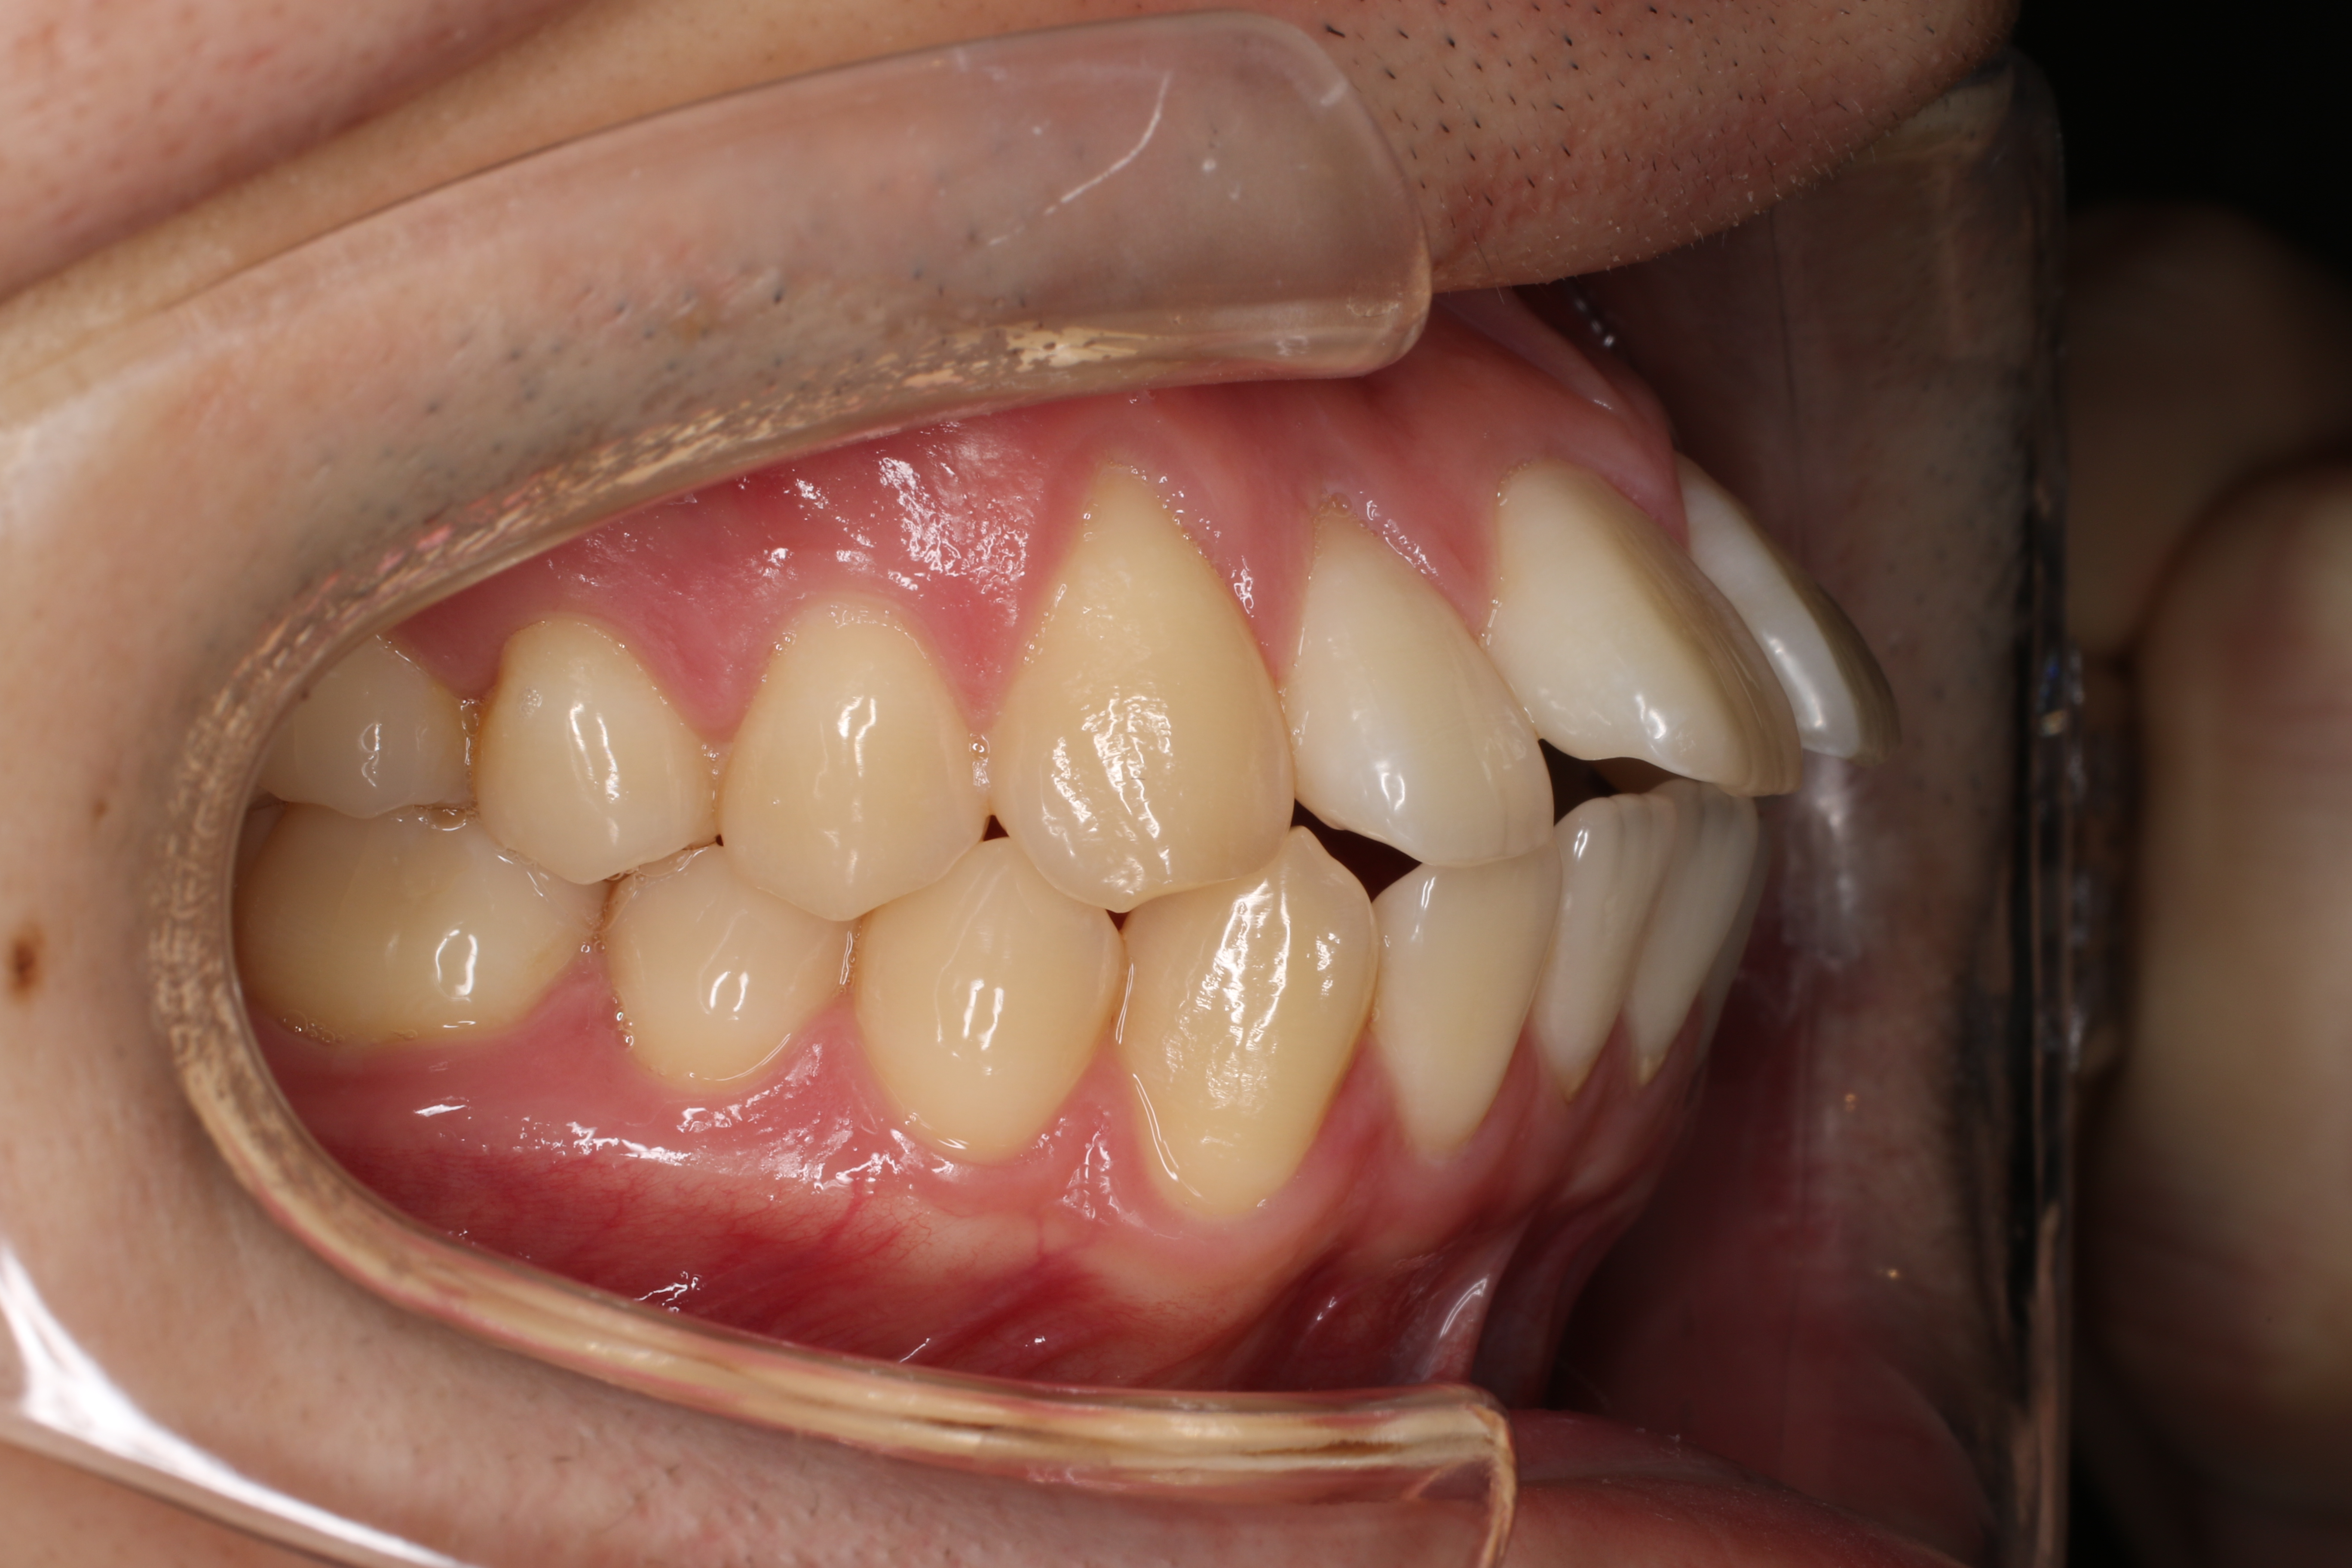

すきっ歯を治したい

年齢層 20代

性別 女性

主訴 【主訴】すきっ歯を治したい 【診断・症状】空隙歯列、1,1正中離開

治療費用 検査・診断:38,500-/裏側矯正治療:1,397,000-(※全て税込)

治療期間 約1年8か月(22回)

抜歯 無(非抜歯)

矯正の装置 裏側矯正(舌側矯正)

副作用、リスク 歯肉退縮,歯根吸収,疼痛,咬合の違和感,装置の違和感,虫歯,歯肉炎

case6_すきっ歯_before

Before

case6_すきっ歯_after

After